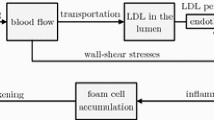

The second part of the model describes the pathways leading from vessel ischemia to accumulation of cells and molecules and hence to plaque development. The considered pathways and interactions are schematically illustrated in Fig. 2.